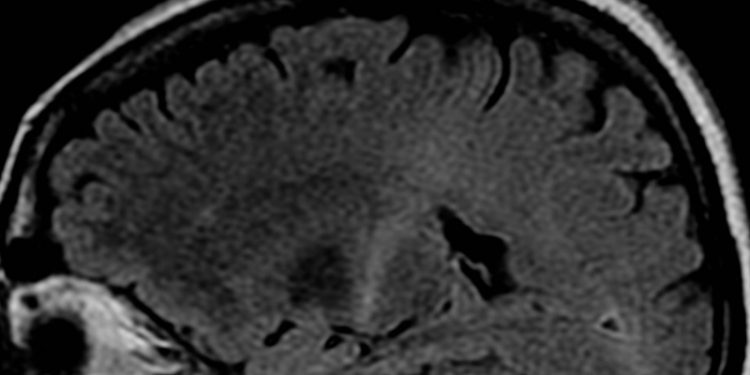

Intracranial Atherosclerosis on 7T MRI and Cognitive Functioning – the SMART-MR study

The individual and societal burden of dementia continues to rise as the global population, on average, grows older. Though it is well known that cerebrovascular disease as a result of intracranial atherosclerosis (ICAS) can contribute to dementia and cognitive decline, less is known about this relationship with regards to premorbid cognitive functioning and the effect of artery-specific lesions. This prospective cohort study used 7 tesla (7T) vessel wall-MRI to explore the association between ICAS and cognitive function among 130 patients (mean [SD] age = 68 [9] years, 88% male) with known vascular disease. Each patient’s neuropsychological status was assessed with a variety of tests, and individual testing scores were averaged to yield a composite Z-score. Imaging revealed that among the cohort, the average ICAS burden for the total circulation (ICASTC) was 8.5±5.7 lesions, for the anterior circulation (ICASAC) 5.3±3.2 lesions, and for the posterior circulation (ICASPC) 3.8±3.0 lesions. No significant association between ICASTC and memory was found (b = -0.02 per +1 lesion, 95% CI -0.05 to 0.00, where b is a linear regression coefficient representing the difference in Z-score per one lesion increase in ICAS burden), even after controlling for age, sex, education level, and reading ability. However, a significant association between ICASPC and memory was observed (b = -0.06 per +1 lesion, 95% CI -0.10 to -0.01). Additionally, when looking at individual arteries, ICAS burden in the posterior cerebral artery (ICASPCA) was associated with significant decline in both memory (b = -0.13 per +1 lesion, 95% CI -0.24 to -0.02) and executive function (b = -0.09 per +1 lesion, 95% CI -0.17 to -0.01). Non-significant associations between ICAS burden in the anterior cerebral artery (ICASACA) and decline in memory and executive function were observed. No significant associations were seen for the middle cerebral, internal carotid, vertebral, or basilar arteries. Overall, this study showed that among patients with a history of vascular disease, high ICAS burden in the posterior circulation as well as the posterior cerebral artery was associated with poorer memory and executive function. These findings may help inform understanding of how atherosclerosis of specific cerebral vessels contributes to the development of dementias.